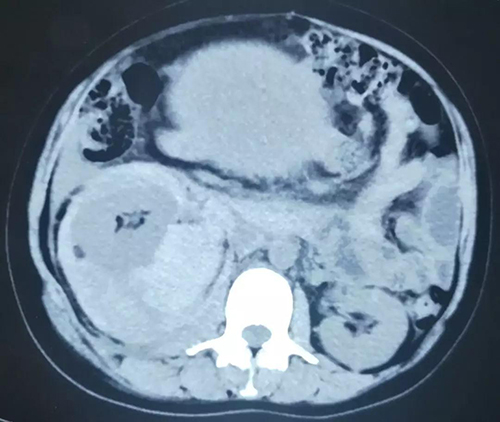

患者为一名诊为结节性硬化症的晚期妊娠女性,1天前突发右侧腰腹部剧痛伴休克于当地医院发现右肾巨大错构瘤(直径约10cm)破裂出血,右侧腹膜后大范围血肿形成,血红蛋白进行性下降,病情危急,急诊转至我院。

肾错构瘤亦名肾血管平滑肌脂肪瘤,通常为良性肿瘤。小的病变无症状,常在查体时被发现。大的肿瘤常因自发性破裂导致大出血,出现腰腹部疼痛,严重者可在较短时间内出现休克。该患者为结节性硬化症双肾多发错构瘤,破裂的瘤体较大,出血难以控制,同时合并晚期妊娠,病情十分复杂。